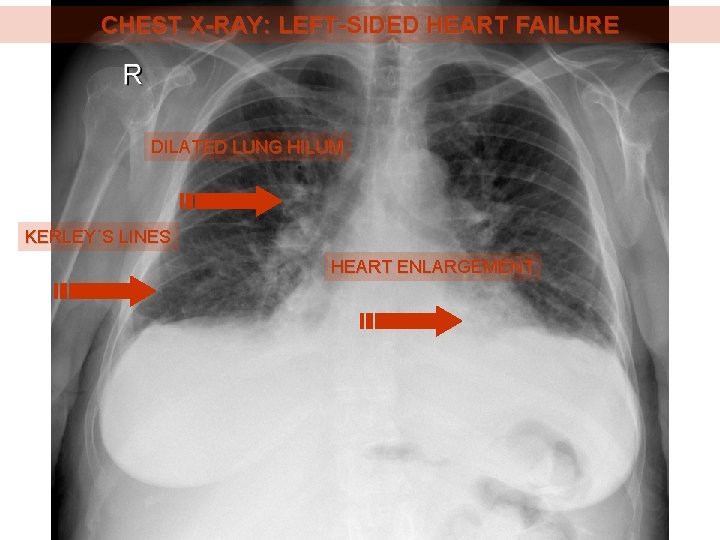

CHEST X-RAY: LEFT-SIDED HEART FAILURE DILATED LUNG HILUM KERLEY´S LINES HEART ENLARGEMENT